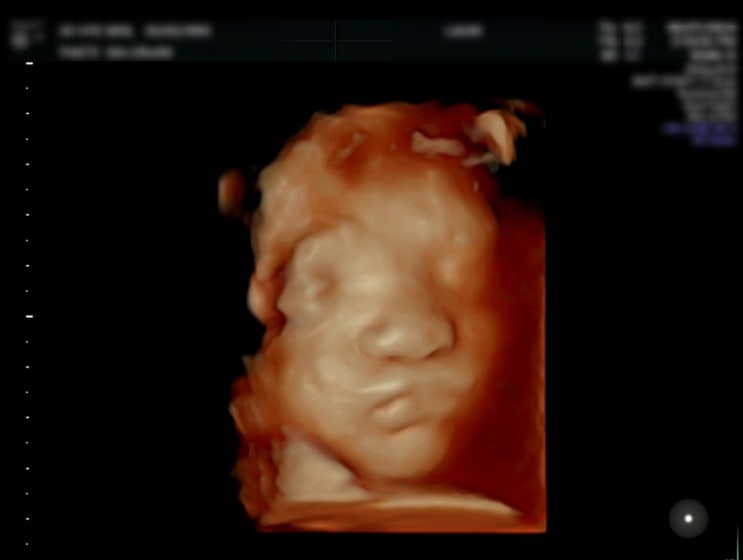

[임신] 임신29주차 입체초음파 태아얼굴확인

이번 검진은 딸랑구 얼굴 보는 날 항상 초음파로 볼 때마다 팔로 귀막고 있었는 데 이번 방문도 그러고 있...